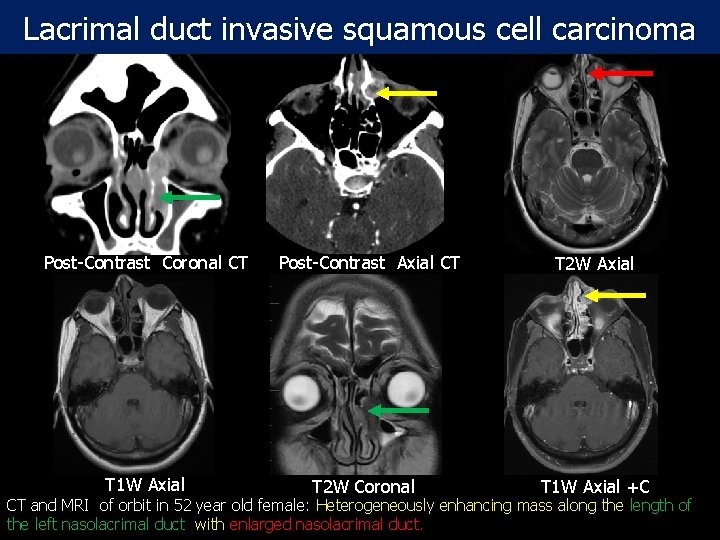

Lacrimal duct invasive squamous cell carcinoma Post-Contrast Coronal CT T 1 W Axial Post-Contrast Axial CT T 2 W Coronal T 2 W Axial T 1 W Axial +C CT and MRI of orbit in 52 year old female: Heterogeneously enhancing mass along the length of the left nasolacrimal duct with enlarged nasolacrimal duct.